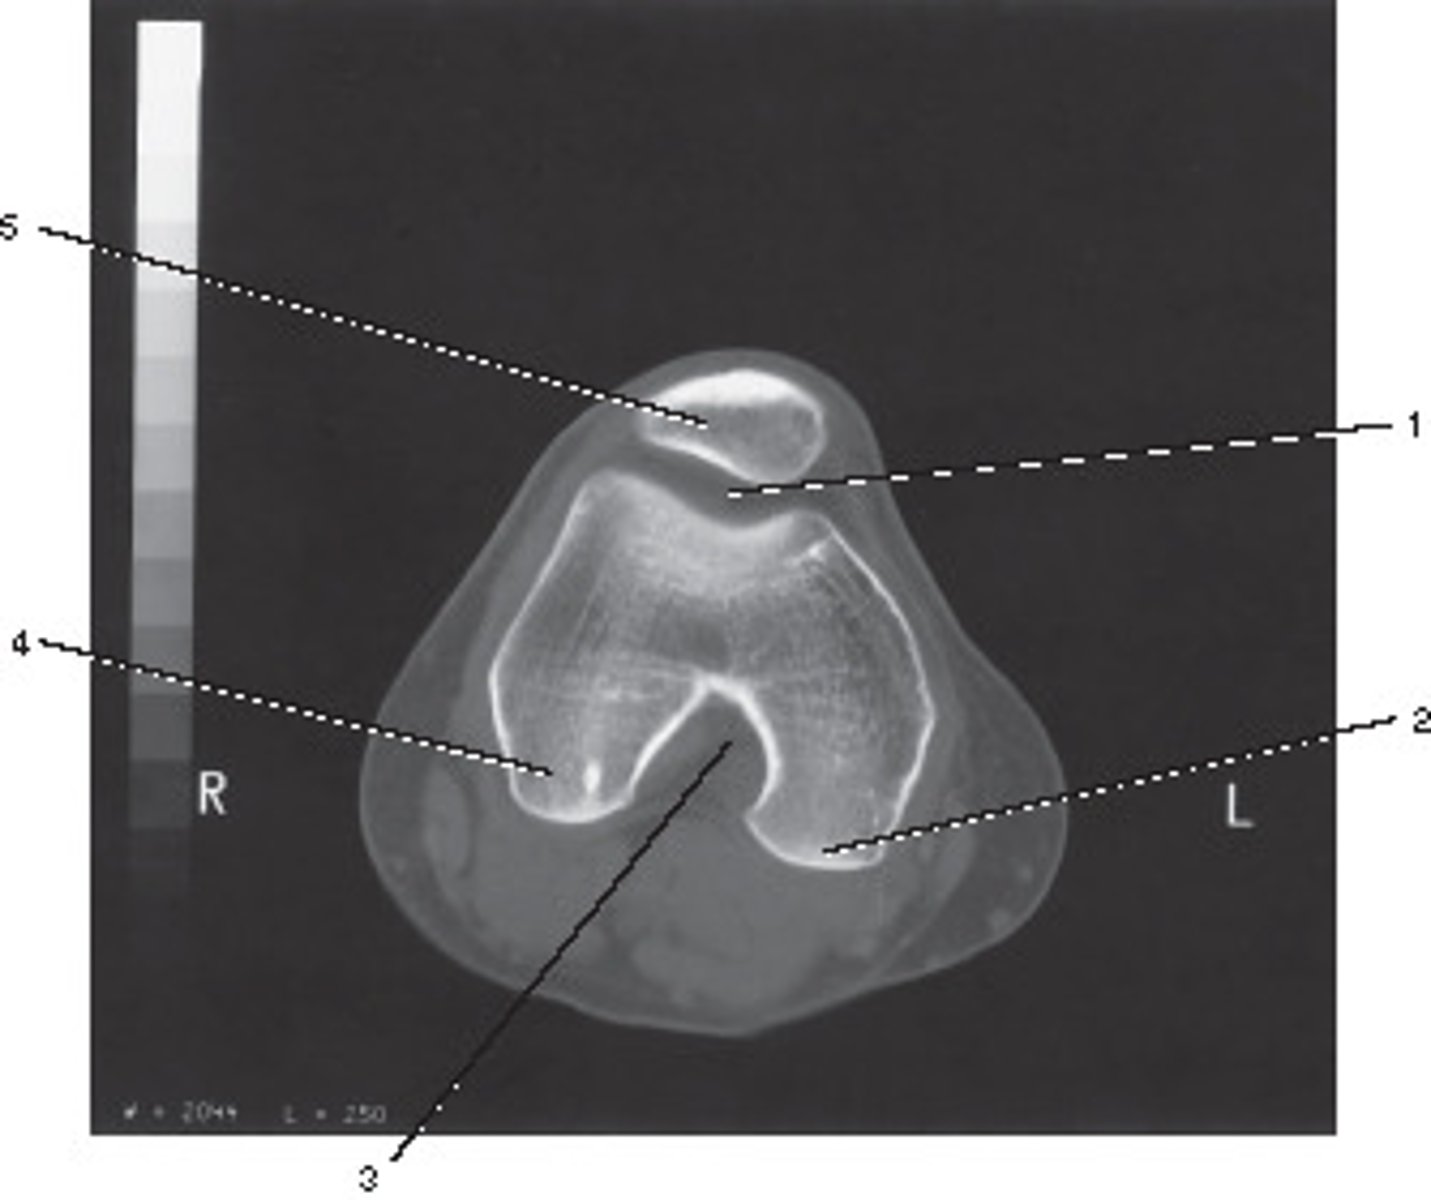

Fibula

Number 1 corresponds to which of the following?

<p>Number 1 corresponds to which of the following?</p>

This image displays what anatomic plane?

<p>This image displays what anatomic plane?</p>

30

Sesamoid Bones

Number 2 corresponds to which of the following?

<p>Number 2 corresponds to which of the following?</p>

Lateral Condyle

Number 4 corresponds to which of the following?

<p>Number 4 corresponds to which of the following?</p>